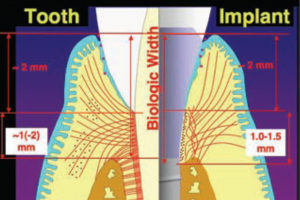

Mielőtt a leírást a második különbség, hogy tisztázni kell egy nagyon fontos pont tekintetében biológiai szélesség (SB).

A „biológiai szélesség” ugyanazt jelenti, mint a fog-fogíny mellékletet. Ahogy közeledik a Apex 3 részből áll:

- Sulkus - sulcus

- epiteliális mellékletet

- kötőszöveti mellékletet

- Biológiai szélessége mintegy fogászati implantátumok és fogorvosi állandó, és körülbelül egyenlő 3 mm. De bárhol implantátumok ez egy kicsit több, mint 3 mm.